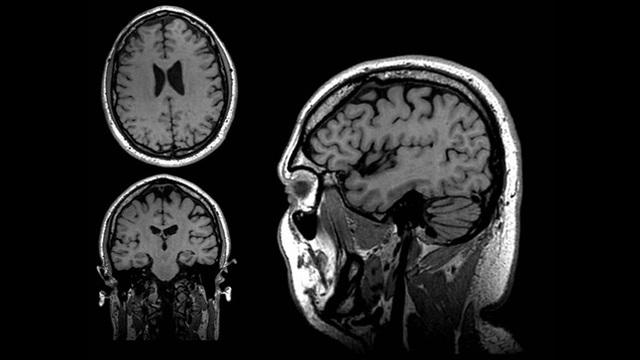

• Resonancia Magnetica

Resonancia Magnetica

-Inventor: Doctor Raymond Damadian

-puede ser usada para detectar enfermedades porque distintos tipos de tejidos emiten señales que varían en su duración, en respuesta al campo magnético.

-Autor: Investigador Paul Lauterbur.

-se crea la primera resonancia magnética en 2 y 3 dimensiones utilizando gradientes.